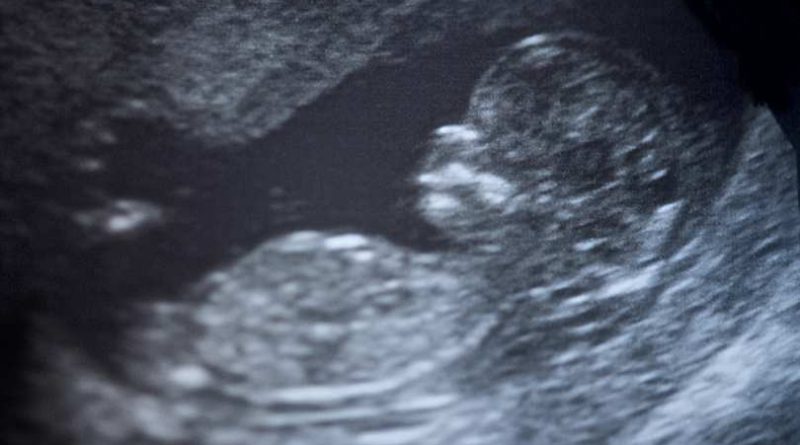

New York Times accidentally reveals humanity of the preborn

Science Matters: Humanity of unborn babies acknowledged by the New York Times in fetal surgery article.